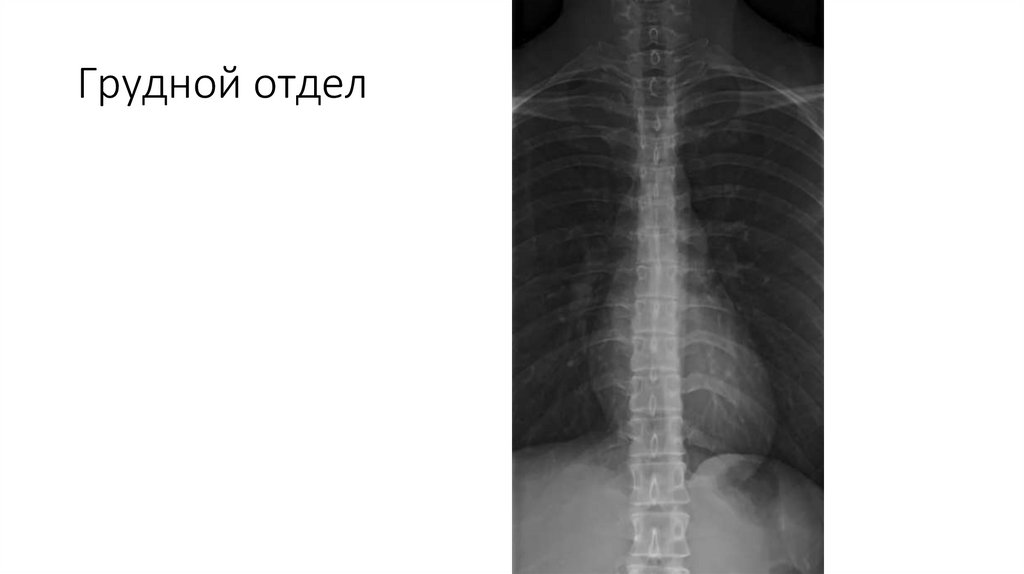

Грудной отдел